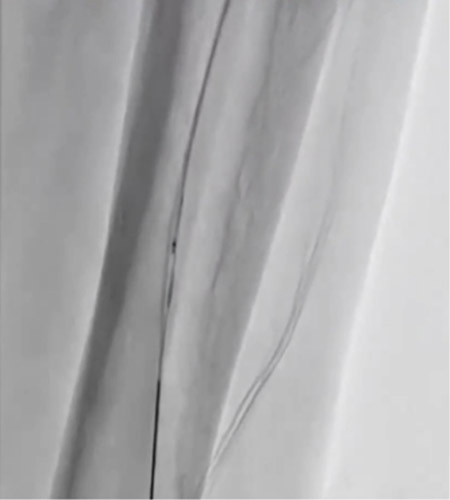

ガイディングシースから造影を行い、SFAの石灰化を伴う短いCTO病変を確認した(図6)。6gワイヤーで石灰化を縫うようにdrillngをし、ワイヤー通過に成功した。血管狭窄部貫通用カテーテルでCTO部分を通過させた後に、4㎜径のバルーンで拡張を行った。OFDIで血管内を観察すると突出する石灰化及び、Distal部分は解離を認めた(図7)がルーメンは確保出来ていた。石灰化部分に4㎜径のcutting balloonで拡張を追加しルーメンは確保(図8)できたが、圧較差は改善しなかったため更にProximal側の病変(図9)に4㎜径のcutting balloonで拡張しDES 7㎜×150㎜を留置した。Distal側はDCB 4㎜×200㎜を施行した。最終造影では病変部は拡張出来ており、圧較差がなくなったことを確認し終了した。(図10)今回の様にPTAは開通しているがATAは閉塞している様な症例でTAIを行う際、PTAからシースを挿入するとPTAも閉塞してしまいCLTIを招いてしまう恐れがある。今回の様な場合は閉塞しているATA経由のTAIを行うことが重要と考える。